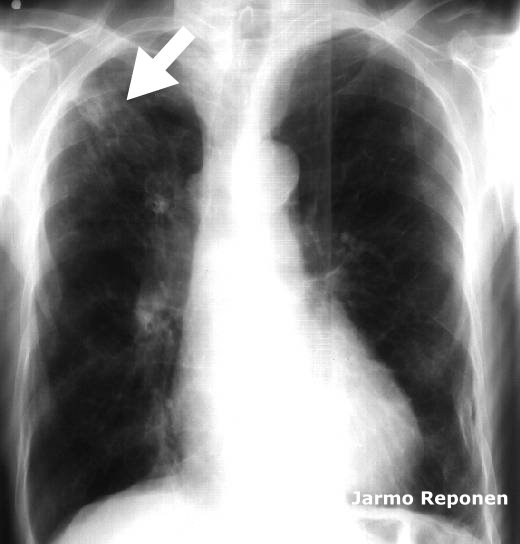

Tuberculosis in Chest x-Ray

Tuberculosis in chest x-ray. Tuberculosis in chest x-ray (arrow)

Picture: Jarmo Reponen